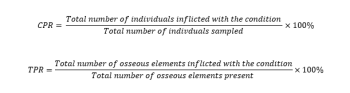

The thoracic and lumbar spine of 44 skeletons was analysed for the macroscopic presence of Schmorl’s nodes. The cervical vertebrae were not analysed as the lesions rarely develop in this region of the spine (Roberts and Manchester 2010). The number of vertebrae present for each skeleton analysed was first determined, followed by the morphological assessment of Schmorl’s nodes on the superior and/or inferior vertebral surfaces, and characterised by a depression with a sclerotic margin (figure 3). The condition was counted once per a vertebra. The system of recording was influenced by the York Osteoarchaeology Ltd and implemented uniformly across the study. The crude prevalence rates (CPR), and true prevalence rates (TPR) of Schmorl’s nodes (Waldron 2017) were calculated using the following equations: